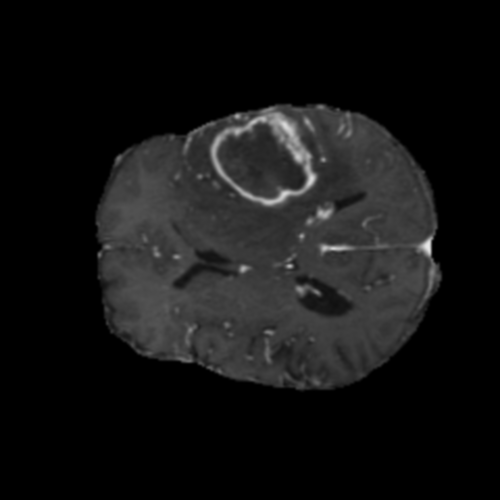

Ejemplos de Modalidades MRI

Visualización de las 4 modalidades de resonancia magnética y las segmentaciones de zonas tumorales utilizadas para entrenar el modelo

Glioma de Alto Grado (HGG)

T1ce HGG

T1ce

Núcleo HGG

Núcleo

Edema HGG

Edema

Realce HGG

Realce

Tumor Completo HGG

Tumor Completo

Núcleo Edema Realce